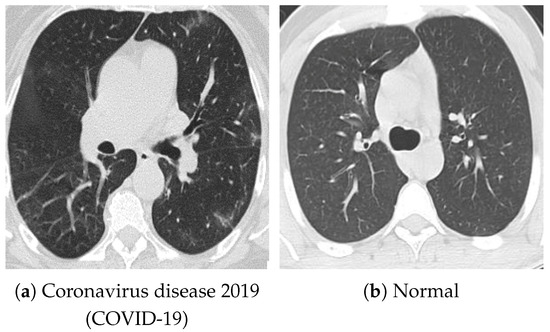

For pretraining, we utilized a subset of the J-MID (https://www.radiology.jp/j-mid/ (accessed on 6 April 2025)) database, which contains large-scale CT scans from Japanese medical institutions, and the RICORD dataset [58], an open dataset that was developed collaboratively by the Radiological Society of North America and international partners and contains chest CT scans collected from four countries. Each dataset was constructed with two domains based on mediastinal and lung window settings in chest CT images. Both domains are denoted as and , and the labels are not used during pretraining. Specifically, for the J-MID subset, (the mediastinal window) contains 31,256 CT images, and (the lung window) contains 26,403 CT images. The RICORD dataset comprises 12,897 (mediastinal window) images and 11,668 (lung window) images for pretraining. For the J-MID dataset, was generated using a window level (WL) of HU and a window width (WW) of HU, whereas was generated using a WL of HU and a WW of HU. For the RICORD dataset, was generated with a WL of HU and a WW of HU, while was generated with a WL of HU and a WW of HU. These parameter ranges were selected to cover clinically standard lung and mediastinal window settings while accommodating inter-scan variability in DICOM metadata. The corresponding images for each example are shown in Figure 2 and Figure 3. For fine-tuning and evaluation, we utilized two public datasets: the SARS-CoV-2 CT-Scan Dataset [59] and the Chest CT-Scan Images Dataset (https://www.kaggle.com/datasets/mohamedhanyyy/chest-ctscan-images (accessed on 6 April 2025)). Both datasets were used for the coronavirus disease 2019 (COVID-19) and chest cancer classification tasks, respectively. The data breakdown is as follows: the SARS-CoV-2 CT-Scan Dataset comprises 1589 training, 397 validation, and 495 test images, labeled into two (COVID-19 and Normal) classes. The Chest CT-Scan Images Dataset comprises 490 training, 123 validation, and 315 test images labeled into four (adenocarcinoma, large-cell carcinoma, squamous-cell carcinoma, and normal) classes. COVID-19 classification and lung cancer classification were selected as downstream tasks because chest CT is widely used in clinical practice for diagnosing both COVID-19 and lung cancer, allowing for an evaluation that closely reflects real-world clinical scenarios. Accordingly, to ensure reproducibility and enable fair comparisons with prior studies, we prioritized the use of publicly available datasets. The corresponding images for each example are shown in Figure 4 and Figure 5.

Figure 4.

Examples of chest CT images on the SARS-CoV-2 CT-Scan dataset: (a) COVID-19 and (b) Normal.